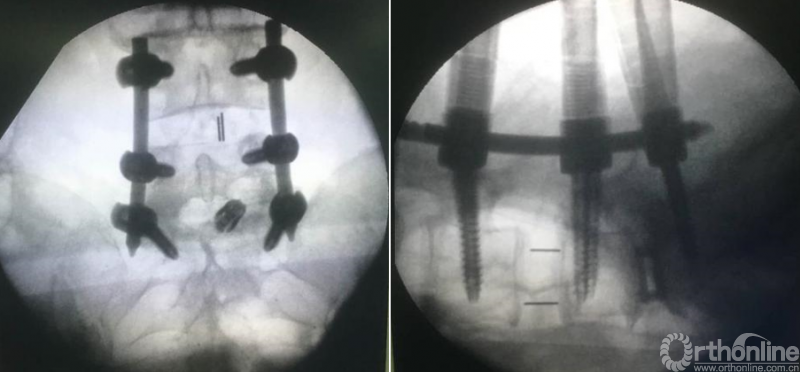

第十步“置”:置入融合器、经皮钉。

第十步“置”:置入融合器、经皮钉。

总的来说,单边双通道镜下融合技术和LUSTA大通道镜下融合技术对于解决腰椎间盘突出症、腰椎管狭窄症合并腰椎不稳以及Ⅱ°以内腰椎滑脱均有显著疗效,两种技术应该平行发展,两架马车应并驾齐驱共同前进。

病例分享:(滑动查看)